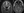

A 3T epilepsy-protocol MRI, including thin-slice T1-weighted, T2-weighted, fluid-attenuated inversion recovery, diffusion-weighted, and susceptibility-weighted imaging, showed a dysplastic anterior temporal pole vs cystic encephalomalacia extending into a sphenoid bone defect along the left cranial fossa, consistent with an encephalocele (Figure). WX was scheduled for epilepsy monitoring unit admission. However, the day before the scheduled admission, WX developed bilateral peripheral vision loss and new bitemporal headaches with associated tinnitus and a positional component as well as clear rhinorrhea. WX was admitted to the general neurology service.

Figure. Left anterior temporal encephalocele: axial (A) and coronal (B) views.